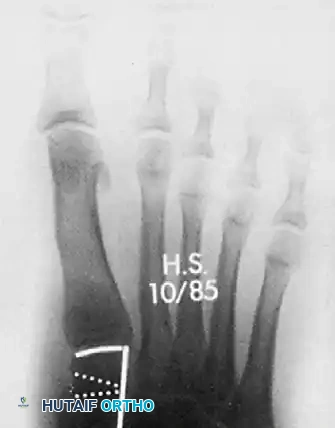

الصور التالية توضح حالة لمريض مراهق يعاني من انحراف شديد، وكيف تم التعامل معها جراحياً ومتابعتها